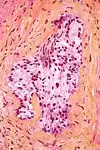

Micrograph demonstrating perineural invasion. HPS stain.